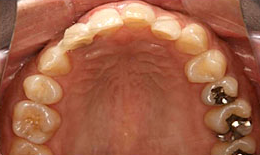

インプラント症例(3)46歳 女性

治療前